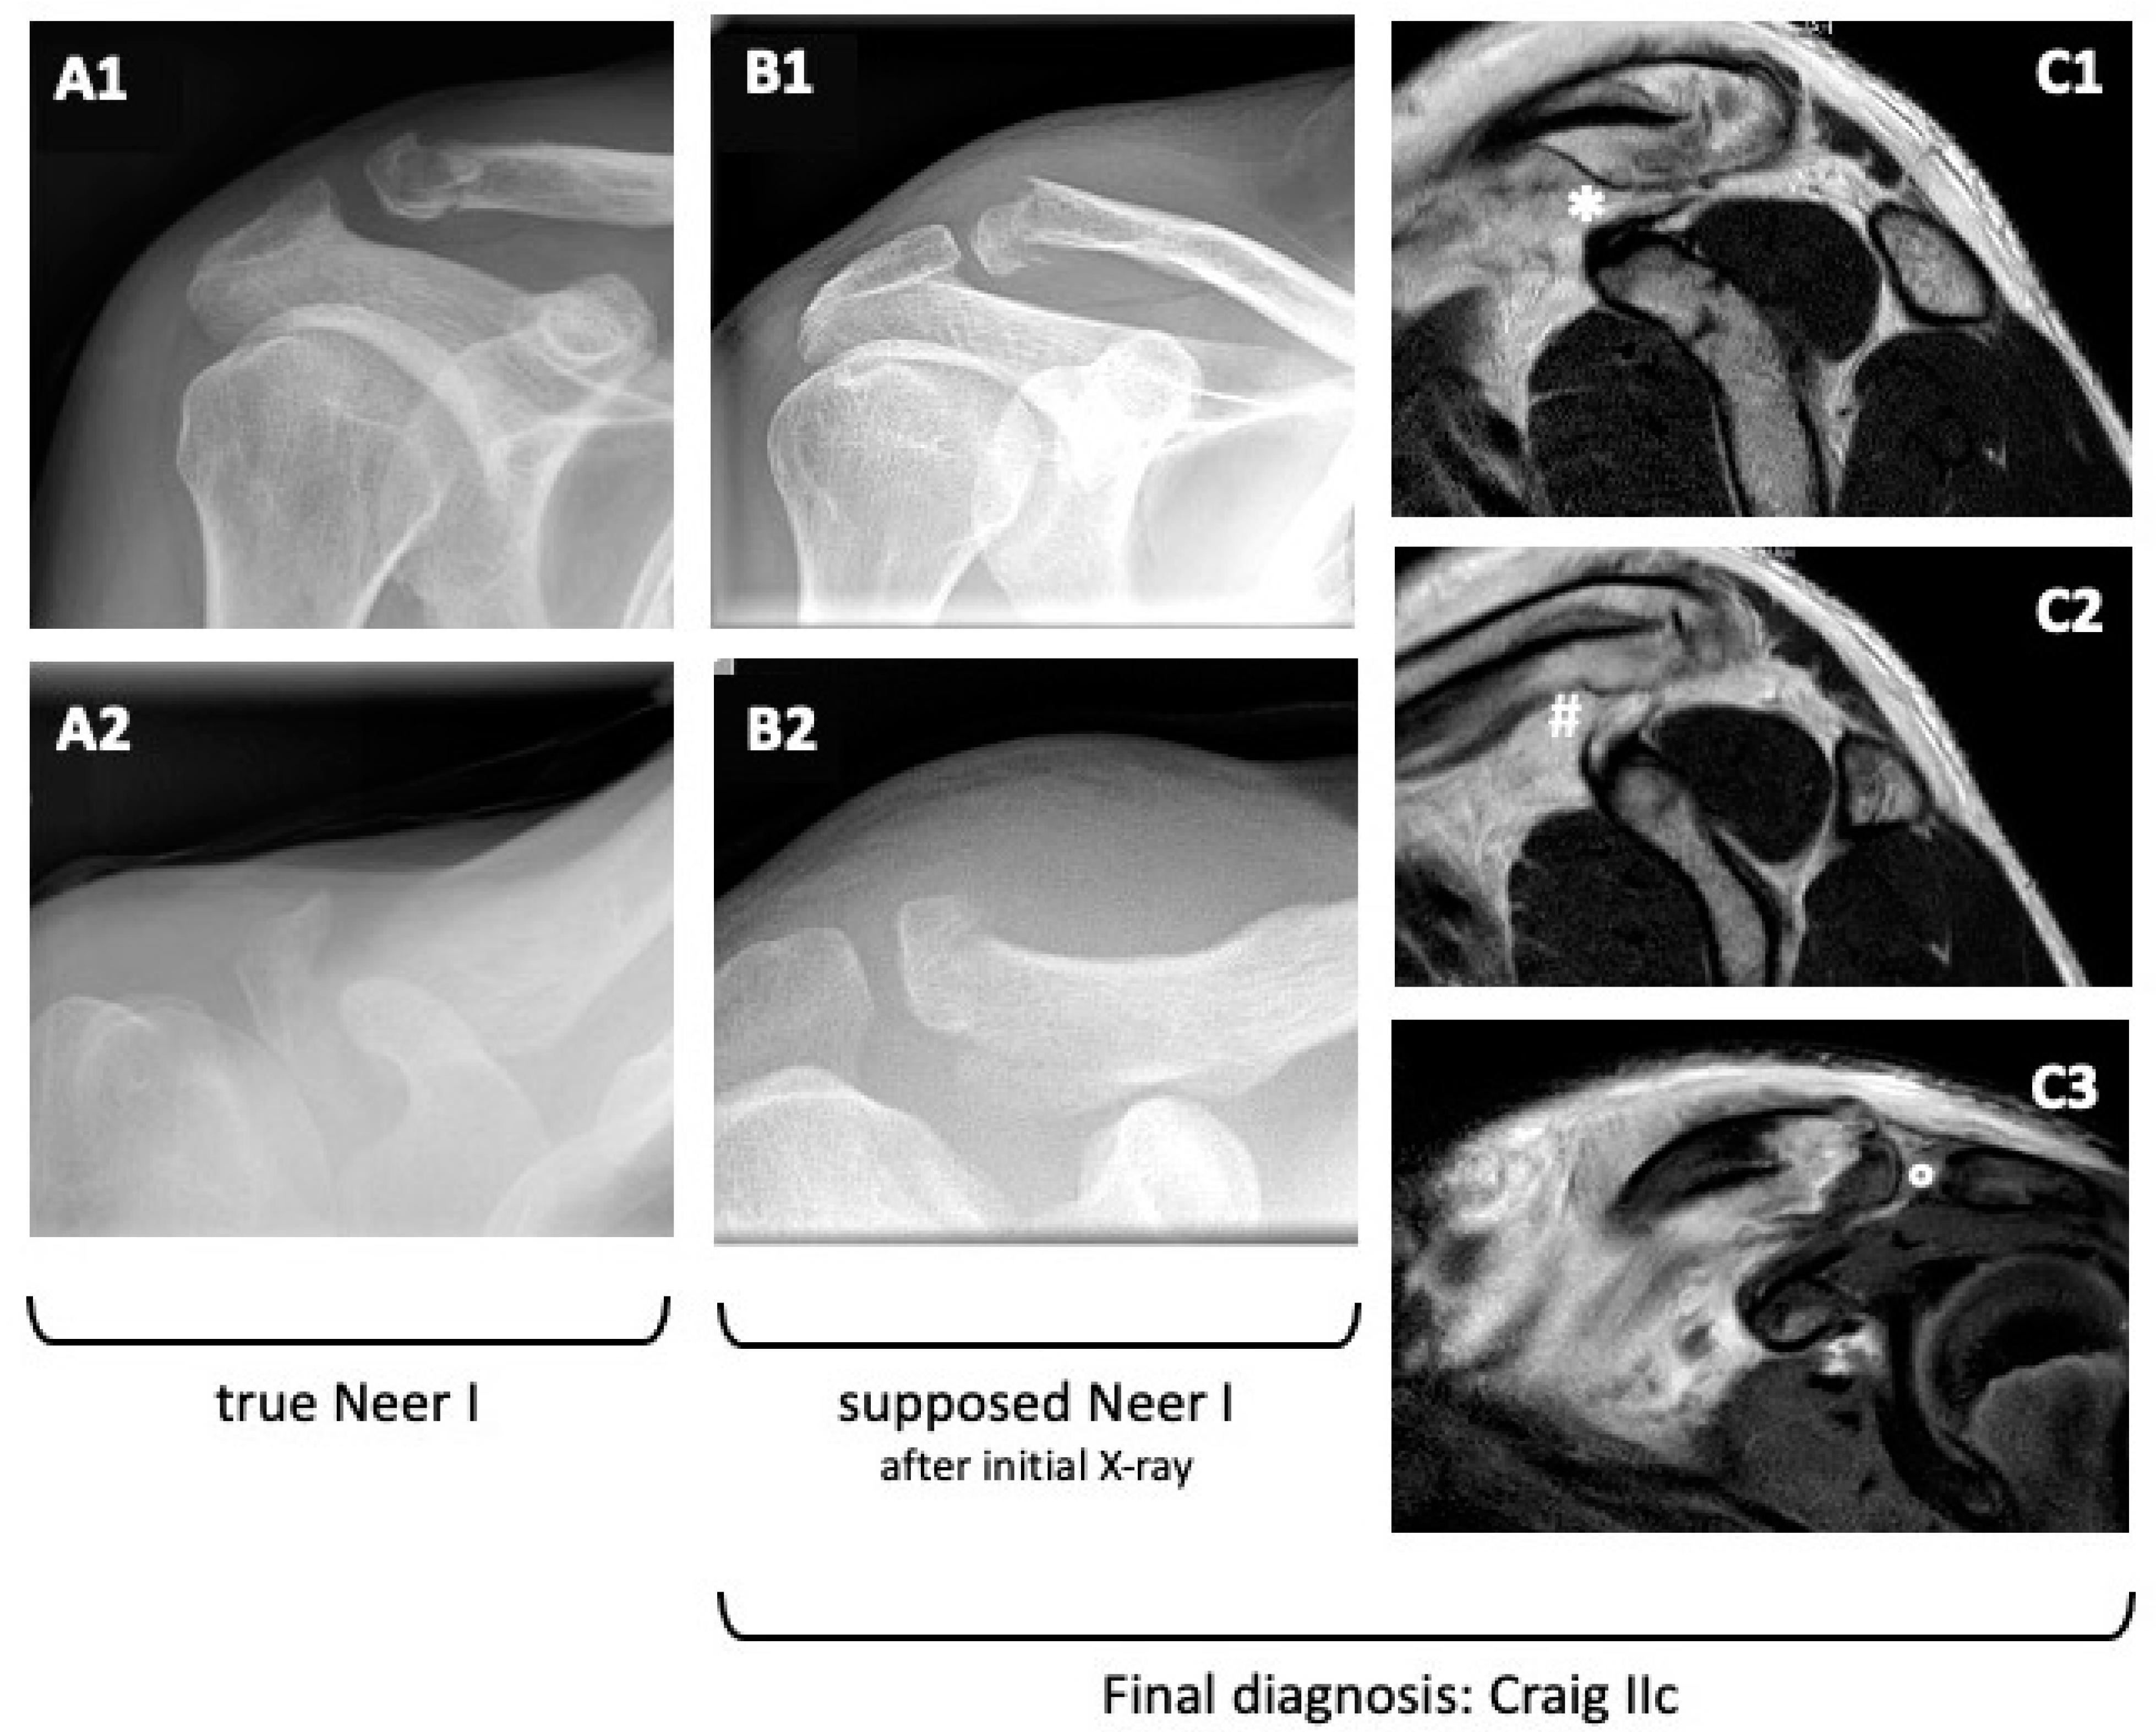

Images A1 and A2 of Figure 2 show exemplary X-rays of the correct fracture configuration of a type I fracture according to the modified Neer classification. Images B1 and B2 show the X-rays of a 28-year-old male. The initial classification was Neer I. An MRI (C1-3) showed a ruptured conoid ligament as well as a ruptured trapezoid ligament. The acromioclavicular capsule and ligament were intact. Thus, by definition, this is an unstable fracture of type Craig IIc.

Figure 2. (A1,A2): Exemplary X-rays of a type I fracture according to the modified Neer classification. (B1,B2): X-rays of a fracture initially classified as Neer I (time [A]). (C1C3): MRI of the fracture shown in (B1,B2). It shows a ruptured conoid ligament [#] as well as a ruptured trapezoid ligament [*] but an intact acromioclavicular capsule and ligament [°]. Thus, by definition, this is an unstable type of Craig IIc.